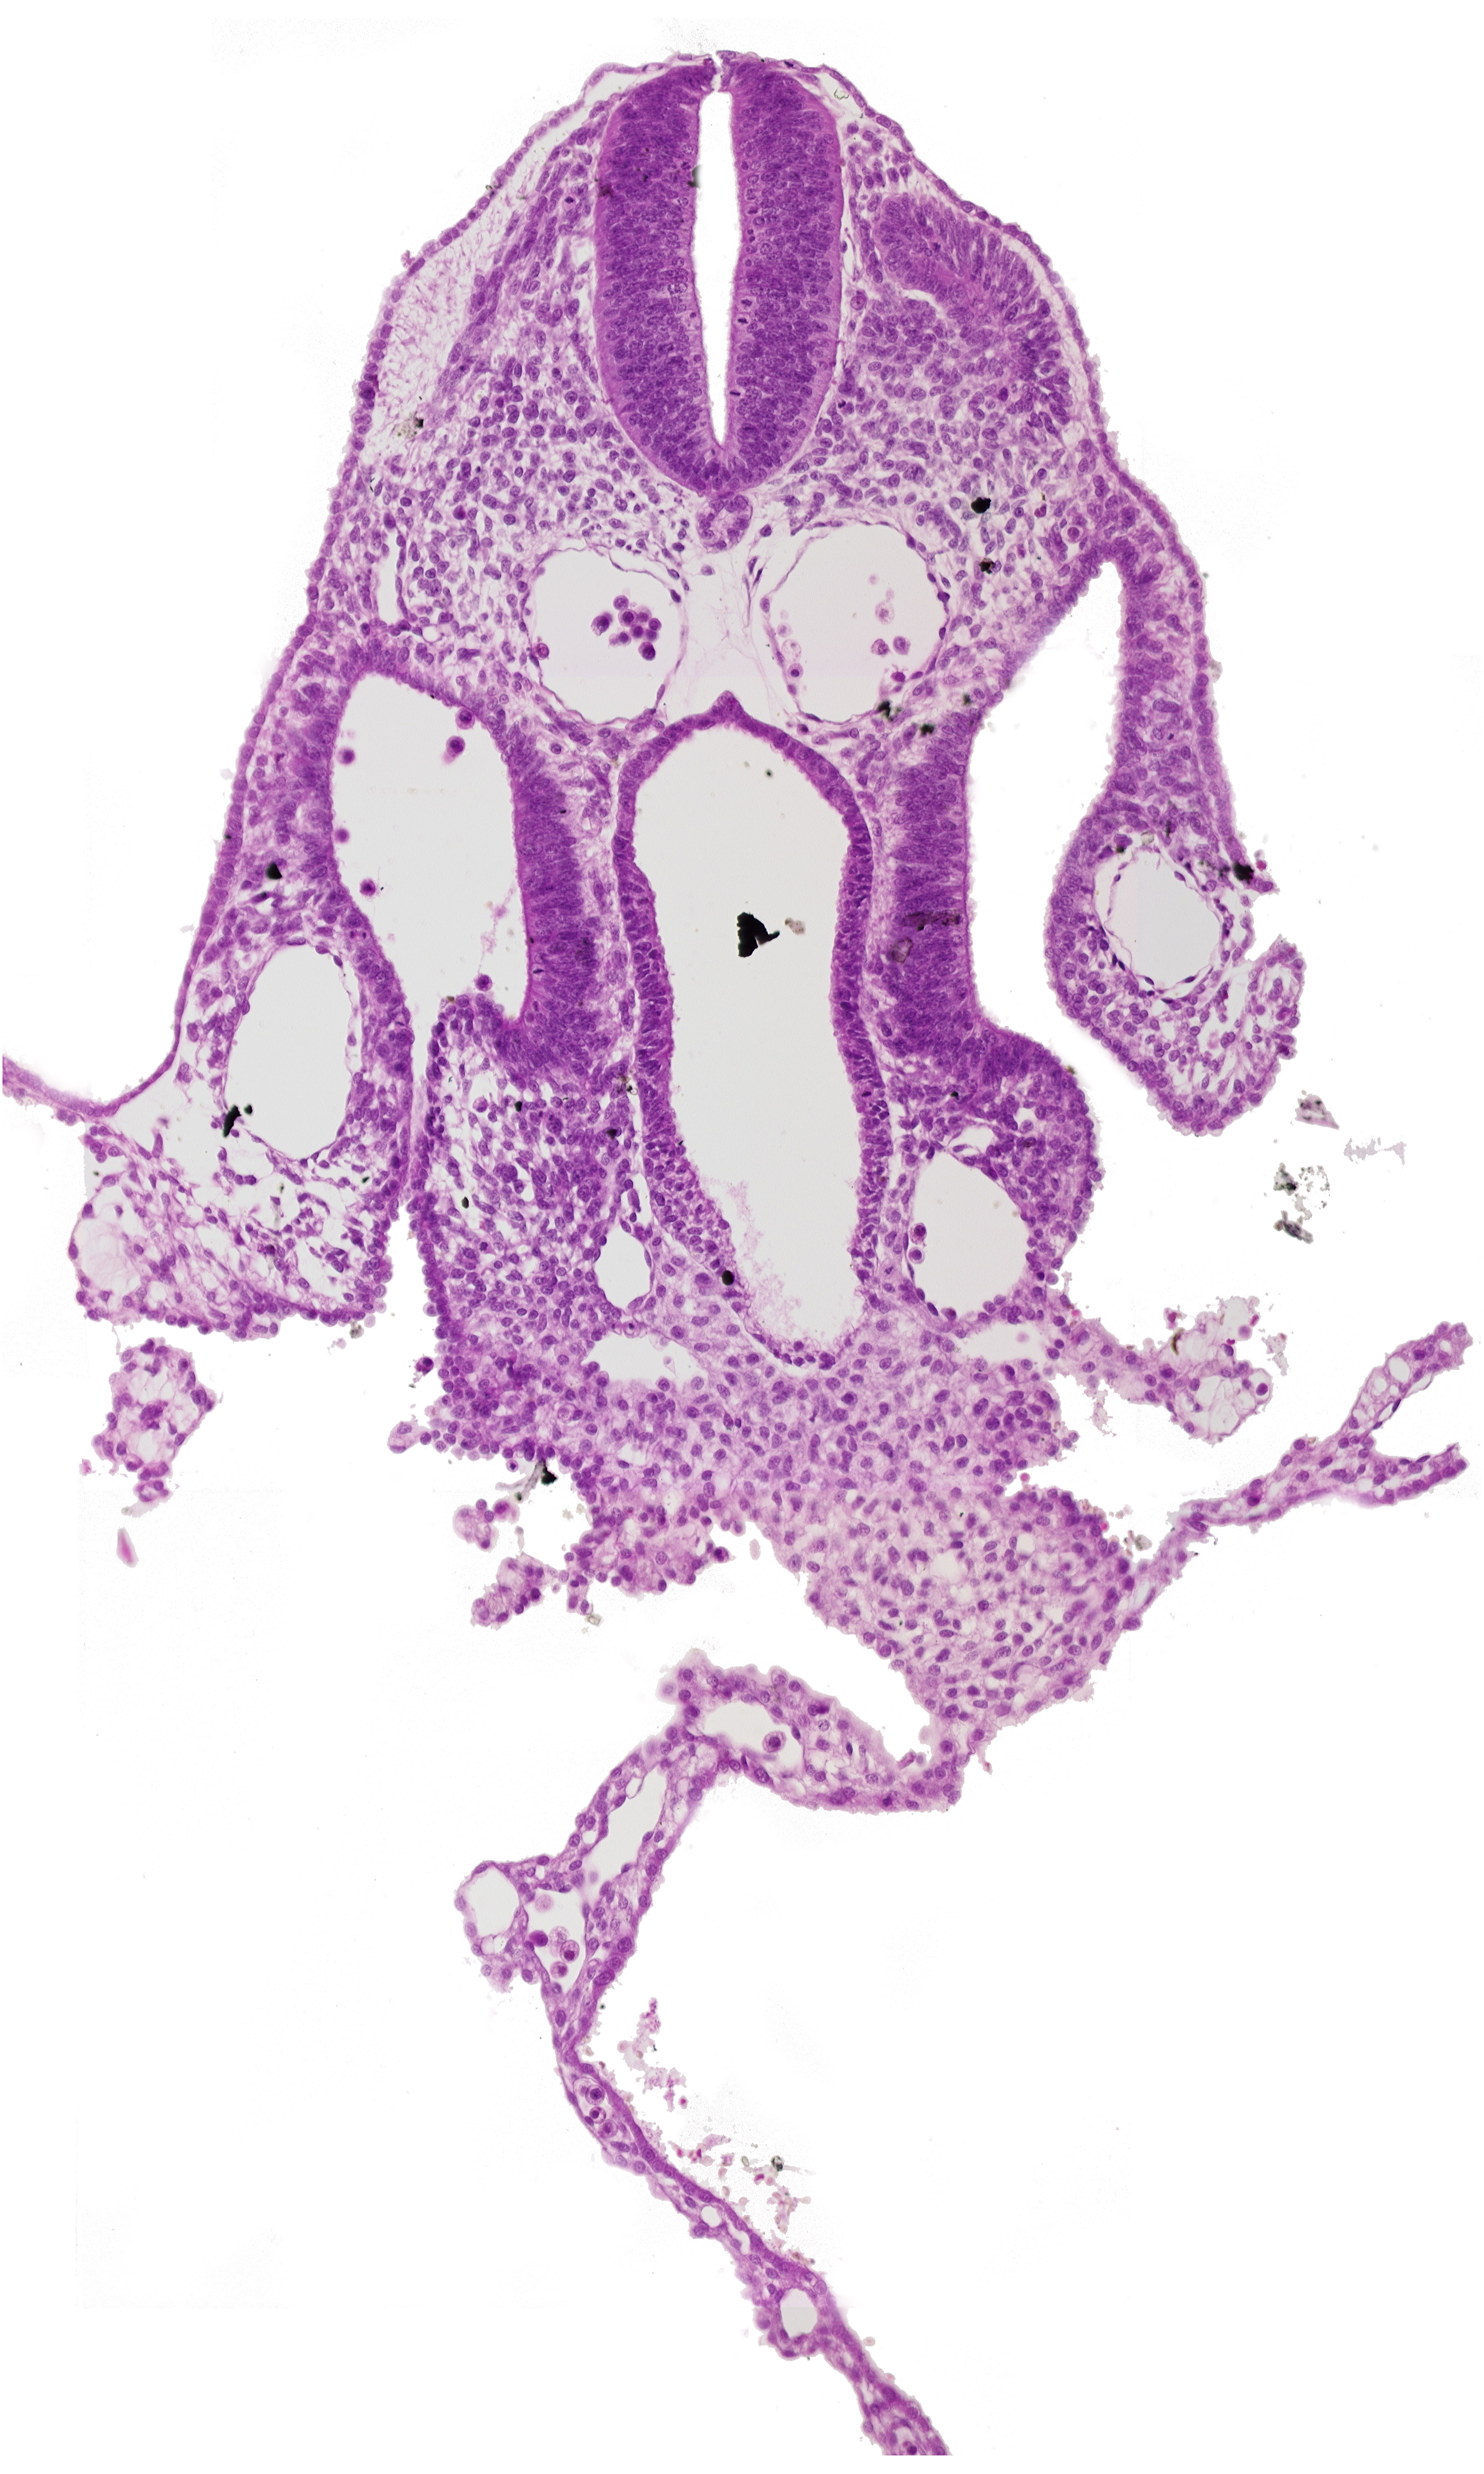

Carnegie Embryo #8943   |   Location: 05-05-02

Keywords: amnion attachment, communication between peritoneal cavity and extra-embryonic coelom, dermatomyotome 7 (C-3), dorsal aorta, extra-embryonic coelom, left umbilical vein, mesothelium of umbilical vesicle, midgut, notochord, right umbilical vein, septum transversum, umbilical vesicle wall